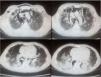

We report the case of a 10 year-old caucasian boy, who presented to the emergency room with an eight-month history of fever, photosensitivity, cutaneous lesions on hands and face, arthralgia, proximal muscular weakness, significant weight loss (10kg), dyspnea on minimal exertion and dysphonia. The patient was previously healthy, with no personal history of pulmonary disease or tuberculosis. Initial physical examination showed tachycardia, tachypnea, decreased breath sounds at pulmonary bases and diffuse crepitations. He also had heliotrope and Gottron's papules (on the hands, elbows and knees), malar rash, Raynaud's phenomenon, and arthritis in the 3rd right proximal interphalangeal joint (Fig. 1). The Childhood Myositis Assessment Scale(CMAS) score (which assesses the patient's overall muscular strength, with a maximum score of 52) was 15. Laboratory work-up showed elevated muscle enzymes (creatine phosphokinase and aspartate aminotransferase), negative anti-nuclear antibody, negative antibodies to extractable nuclear antigens (ENA), negative double-stranded native DNA and negative anti-neutrophil cytoplasm antibody (ANCA). Specific myositis antibodies were unavailable for testing. Based on the presumed diagnosis of JDM, he received intravenous pulse of methylprednisolone and subcutaneous methotrexate. On the first day of hospitalization, the patient suddenly developed cough, worsened respiratory distress and palpable cervical emphysema. An urgent computed tomography scan showed bilateral mild pneumothorax, extensive PNM with subcutaneous emphysema and bilateral pulmonary consolidations, more prominent in bases, associated with ground-glass attenuation areas (Fig. 2). Treatment was with conservative, as well as broad spectrum antibiotics due to impossibility of exclude infection, but respiratory distress worsened at day fifteen. Intravenous immunoglobulin was administered, with no response, and he also started sulfamethoxazole+trimethoprim due to leukopenia. The patient was submitted to orotracheal intubation and drainage of PNM, with no significant improvement. By this time, pneumothorax had improved just with conservative measures. However, despite mechanical ventilation support and management of shock the refractory hypoxemia continued and he died after 23 days of hospitalization.

Although JDM affects primarily the muscles and skin, it can involve many tissues and organs, including the lungs.2,5–7 Lung disease can present as aspiration pneumonia, interstitial lung disease (ILD) or respiratory muscle weakness.5 There are limited data regarding the occurrence of PNM in JDM due to its rarity; its frequency in adults with inflammatory myopathies varies in the literature, but the largest cohort reported a prevalence of 2.2 %.5 Risk factors for the occurrence of PNM in DM are: history of ILD, early age of onset (below twenty years old), cutaneous vasculopathy, normal or slightly increased levels of muscle enzymes (amyopathic dermatomyositis), previous use of glucocorticoids and the presence of anti-MDA52. There is no data for risk factors in JDM. The findings on his CT-scan were also suggestive of ILD, although infection was an important differential diagnosis. The main risk factor for DM-associated PNM is the presence of ILD, with a prevalence of 10–43 % in adult patients2; in pediatric patients, Sato et al. recently reported a prevalence of 27.6 %.7 ILD was diagnosed in all patients with DM-associated PNM,2,5,6 and while ILD is considered a poor prognostic factor,2,5,6 isolated spontaneous PNM did not correlate with increased mortality.5 The global mortality rate of DM-associated PNM is 37.5–52.5 %.2 There is no standardized treatment for DM-associated PNM. In most cases, initial treatment was high-dose methylprednisolone, followed by numerous immunosuppressors.2,5,6